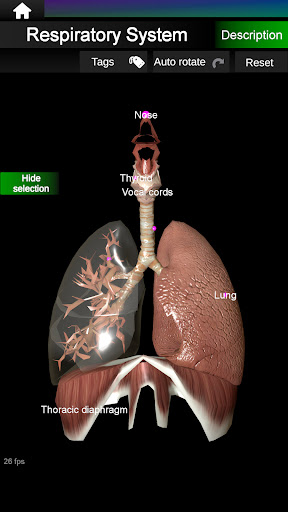

يمكنك هنا تنزيل ملف حزمة تطبيق أندرويد "Internal Organs 3D Anatomy" الخاصة بجهازVodafone Smart N9 Lite مجانًا، نسخة ملف حزمة تطبيق أندرويد - 3.4 للتحميل على Vodafone Smart N9 Lite اضغط ببساطة على هذا الزر. إنه سهل وآمن. نحن نقدم فقط ملفات حزمة تطبيق أندرويد الأصلية. إذا انتهكت أية مواد موجودة في الموقع حقوقك قم بإبلاغنا من خلال